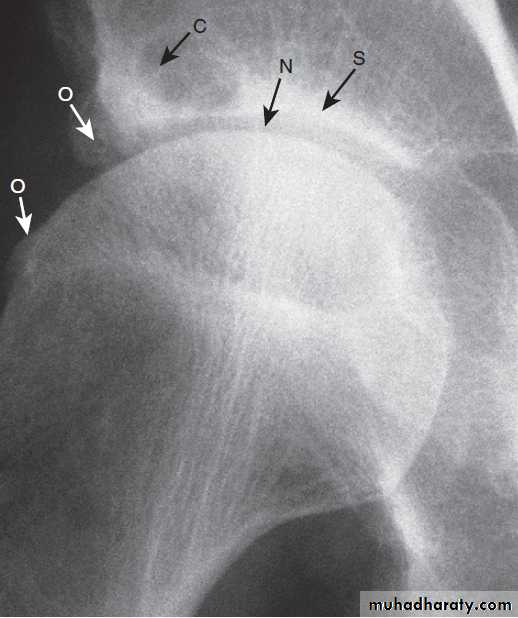

X-ray of hip showing changes of osteoarthritis. Note

the superior joint space narrowing (N), subchondral sclerosis (S), marginalosteophytes (white arrows) and cysts (C).